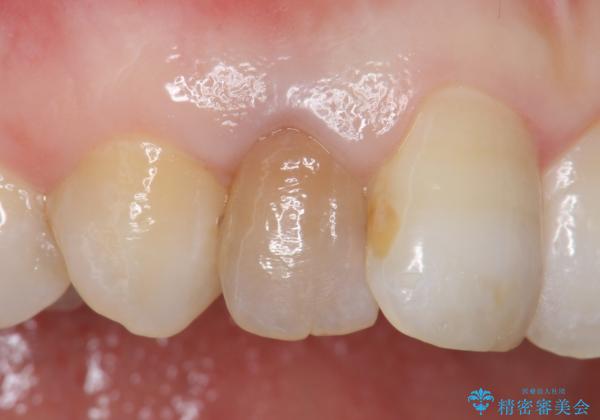

- 右上2番目の歯の変色が気になるといらっしゃった方の症例です。

再根管治療終了後、オールセラミッククラウンによる補綴を行いました。

今回用いたオールセラミッククラウンはジルコニアフレームという白い素材の上にセラミックを盛っているため、審美性が非常に高いのが特徴です。

また、ジルコニアは人工ダイヤモンドの材料にも使われているほど高い強度を持っており、そのためオールセラミッククラウンは審美性だけでなく、奥歯やブリッジの補綴も可能とするクラウンです。